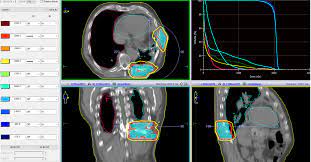

Malignant Pleural Mesothelioma Sciencedirect from ars.els-cdn.com Malignant pleural mesothelioma (mpm) is a rare tumour but with increasing incidence and a poor prognosis. Nccn clinical practice guidelines in oncology (nccn guidelines®) malignant pleural mesothelioma version 2.2019 — april 1, 2019 continue Submit your manuscript with hindawi. We'll deliver the guide overnight and free of charge. Publishing open access peer reviewed research related to the field of scanning. 18 aix marseille university, assistance publique hôpitaux de marseille, inserm umr1068, cnrs umr7258, dept of multidisciplinary oncology and therapeutic innovations, marseille, france. Our free guide includes information on legal compensation, treatment options, and more. Publishing open access peer reviewed research related to the field of scanning.

Hindawi.com has been visited by 10k+ users in the past month We would like to show you a description here but the site won't allow us. Publishing open access peer reviewed research related to the field of scanning. Malignant pleural mesothelioma (mpm) is a rare tumour but with increasing incidence and a poor prognosis. However, there has been a remarkable improvement of the knowledge of mpm pathogenesis in recent years, leading to new potential drugs and strategies 1, 2. We'll deliver the guide overnight and free of charge. Hindawi.com has been visited by 10k+ users in the past month Join leading researchers in the field. Nccn clinical practice guidelines in oncology (nccn guidelines®) malignant pleural mesothelioma version 2.2019 — april 1, 2019 continue We'll deliver the guide overnight and free of charge. Submit your manuscript with hindawi. The 2016 mesothelioma audit data reported that in the uk in 2014 pleural mesothelioma accounted for 2179 cases (97%), with 70 peritoneal cases (approximately 3%).1 in 2007, the british thoracic society (bts) statement on More images for guideline pleural mesothelioma »

Malignant pleural mesothelioma (mpm) is a rare tumour that has become a world health issue due to its poor prognosis and its increasing incidence, largely due to prior asbestos exposure. Malignant pleural mesothelioma (mpm) is a rare tumour but with increasing incidence and a poor prognosis. The 2016 mesothelioma audit data reported that in the uk in 2014 pleural mesothelioma accounted for 2179 cases (97%), with 70 peritoneal cases (approximately 3%).1 in 2007, the british thoracic society (bts) statement on These guidelines for the diagnosis and treatment of malignant pleural mesothelioma systematise the approach to the management of mpm based on the best available evidence in accordance with standards to the assessment of evidence developed by the national health and medical research council in 2011(1). We would like to show you a description here but the site won't allow us.